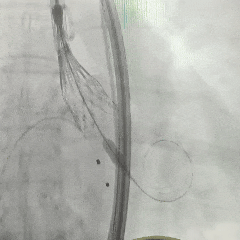

手术过程

左侧冠脉造影

右侧冠脉造影并行PCI

根部造影

可见瓣叶钙化,伴反流

TF21瓣膜0位初始释放

全展开后多角度根部造影:瓣膜深度形态合适,冠脉灌注良好,少量瓣周漏,选择解锁脱钩

脱钩后造影评估:瓣膜深度可,展开良好,少量瓣周漏

外周造影检查,血管无损伤